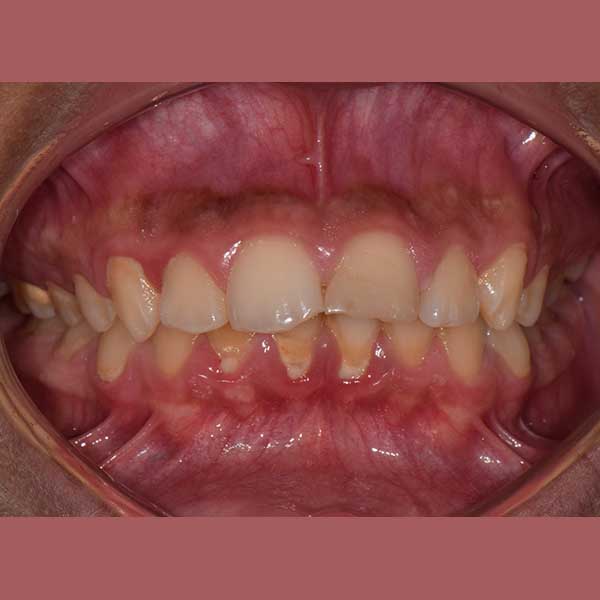

This little kid was suffering from severe protrusion (there was a space between the upper and lower front teeth), and regression in the lower jaw.

The condition was treated by fixed orthodontics and a functional device that serves to advance the lower teeth and the bearing bone forward and stimulate the advancement of the lower jaw forward and Put the upper teeth back.

The case was successfully treated without tooth extraction, as is usual in some similar cases.